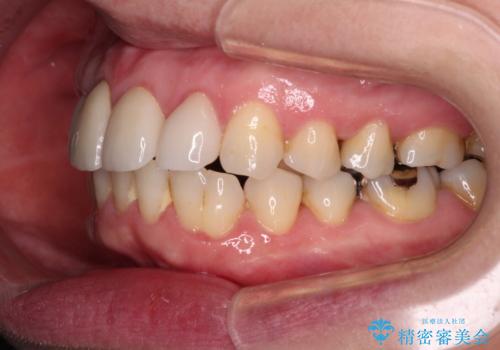

また、当初は予定しておりませんでしたが、歯列が整ったことで前歯の歯の色や形が気になり、矯正治療後にオールセラミッククラウンにて補綴治療することとしました。

あっという間に気になっていた歯列が改善され、自然な口元になり、患者様には大変満足していただきました。